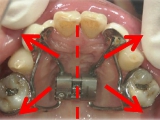

● 臼歯部の後方移動

臼歯を後方に牽引し、移動させることでスペースを確保し歯列を整えます。

臼歯にリンガルアーチという装置を装着し、ミニインプラントを固定源に臼歯を後方に牽引します。

臼歯が後方に下がり、臼歯と小臼歯の間にスペースができました。唇側にワイヤ-をSETし、前歯の歯並びの改善を併行して行います。